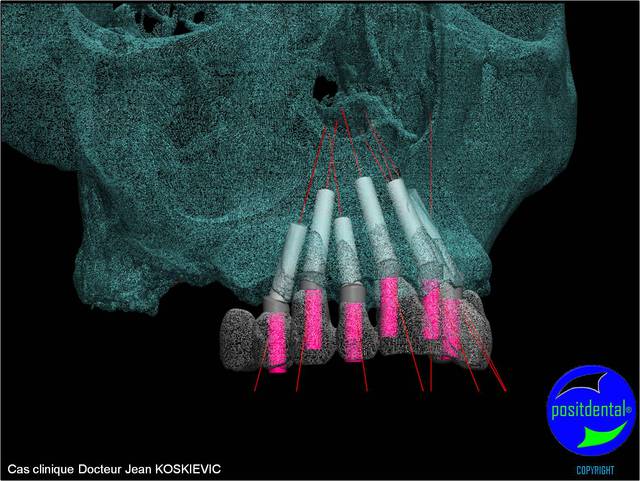

rendu 3D maxillaire sup, pano et photo

et la projet 10 implants maxillaire sup